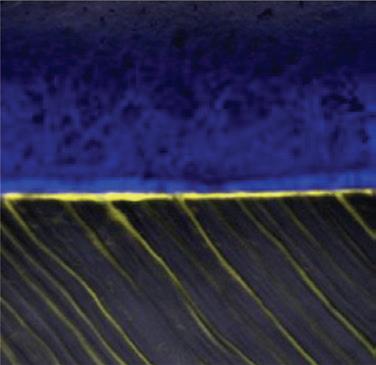

STELA GAP-FREE BONDING INTERFACE

A confocal micrograph of a gap-free Stela-dentine interface. Note the penetration depth of Stela Primer (yellow) within the dentine tubules.

Source: Dr Salvatore Sauro